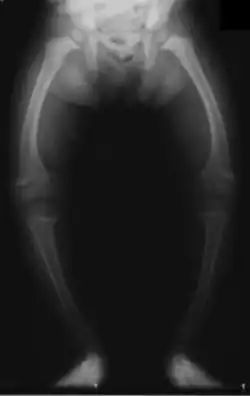

Im zweiten bis dritten Lebensmonat zeigen sich die ersten Symptome in Form von Unruhe, Schreckhaftigkeit, vermehrtem Schwitzen und dadurch ausgelöstem juckendem Hautausschlag (Miliaria). Etwa einen Monat später kommen eine Muskelschwäche mit Froschbauch, Verstopfungsneigung (Obstipation) und erste Knochenerweichungen am Schädel (Kraniotabes) hinzu. Jetzt kann der Calciummangel zusätzlich zu gesteigerter Muskelerregbarkeit (Tetanie) bis hin zu Krämpfen führen. Wiederum etwa einen Monat später entsteht durch Abflachung des Hinterkopfes und Auftreibung der Schädelnähte (Epiphytenbildung) das Bild eines Quadratschädels. Die perlschnurartig aufgereihten Auftreibungen der Knorpel-Knochen-Grenzen an den Wachstumsfugen der Rippen am Brustkorb wird auch Rosenkranz genannt. Auch Hand- und Fußgelenke verbreitern sich durch Auftreibung der Epiphysen zunehmend (Marfan-Zeichen, „doppelte Glieder“). Später zeigen sich ein verzögerter Zahndurchbruch, Defekte im Zahnschmelz, eine verzögerte Mineralisation der Kieferknochen bis hin zum offenen Biss. Weil der Brustkorb ungewöhnlich weich ist, führt der Muskelzug am Zwerchfellansatz zu einer Einziehung, der Harrison-Furche. Zu den weiteren typischen Knochenverformungen gehören Beinverkrümmungen (O-Beine, Genua vara), wobei die langen Röhrenknochen varisch (nach innen) verbogen sind, und die Fehlstellungen weniger im Gelenk selbst liegen. Bei Erwachsenen sind die Wachstumsfugen schon verschlossen und es kommt bei einem Vitamin-D-Mangel lediglich zu einer Osteomalazie ohne die im Kindesalter so typischen Knochenverformungen.

Knochenfehlstellungen heilen bei Kindern bei der klassischen Rachitis nach Substitution von Vitamin D meist selbständig aus, bei schweren Verformungen der Beine werden allerdings oberschenkellange Schienen empfohlen (Orthesen). Bei den Phosphatmangel-Formen und bei Jugendlichen sind deutlich häufiger Korrekturosteotomien notwendig, bei denen durch eine Knochenkeilentnahme mit anschließender Osteosynthese der Achsfehler korrigiert wird.